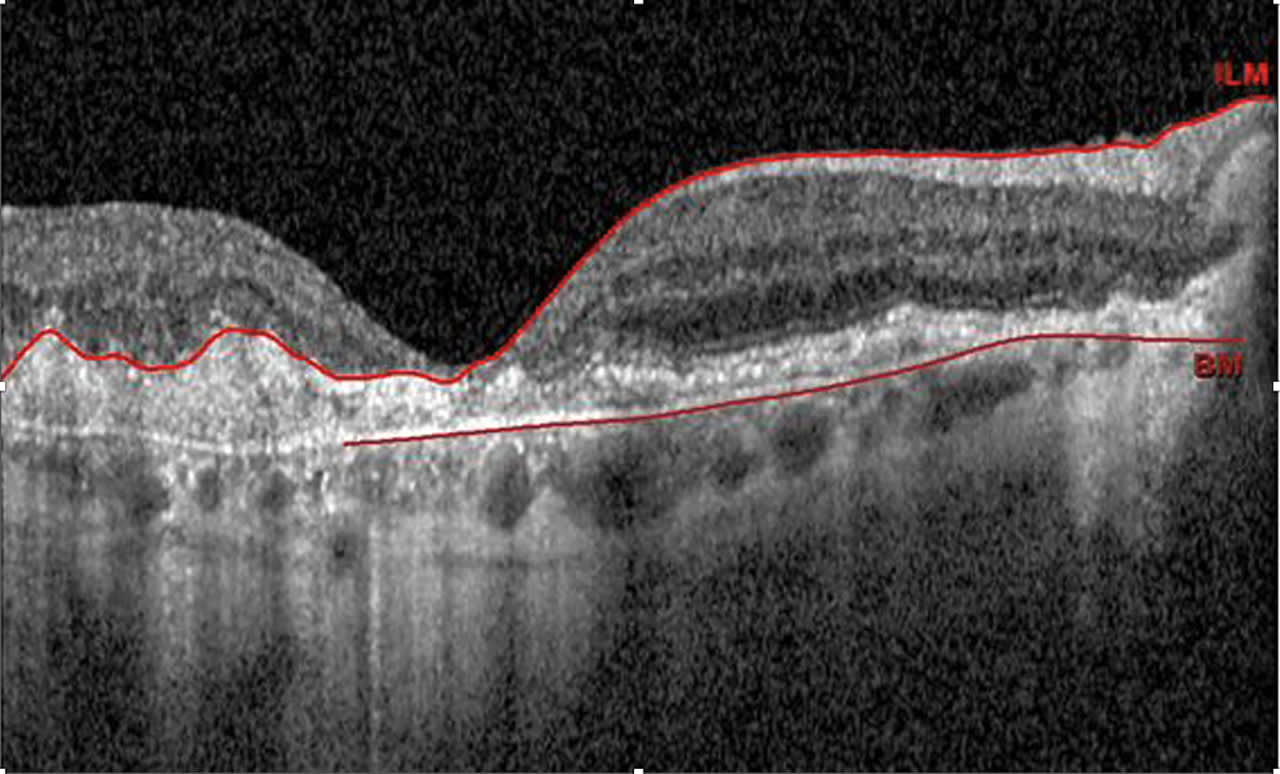

To give one example, I recently had an 81-year-old male patient whose BCVA in his right eye has fluctuated from 20/70-1 to 20/100 over the past two years. An optical coherence tomography (OCT) scan showed foveal encroachment from retinal pigment epithelium atrophy secondary to AMD (Figure 1). The patient, a self-described avid reader, was unhappy at being unable to consistently enjoy his favorite hobby, so we suggested he try the Eye5 device. The patient reported that with the device, he has been able to resume regular reading, which has improved the quality of his life.